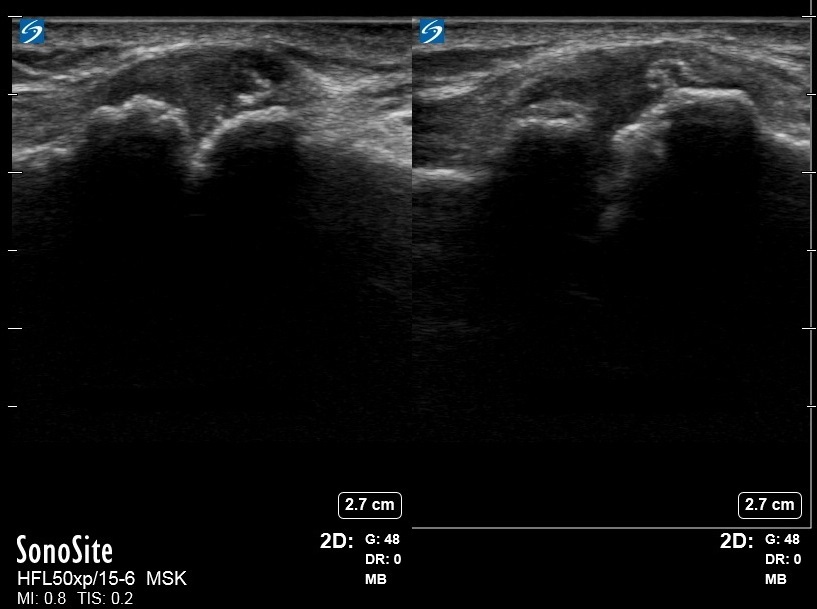

肩変形性関節症の AC ジョイント動的画像

左: 圧縮

右:中立